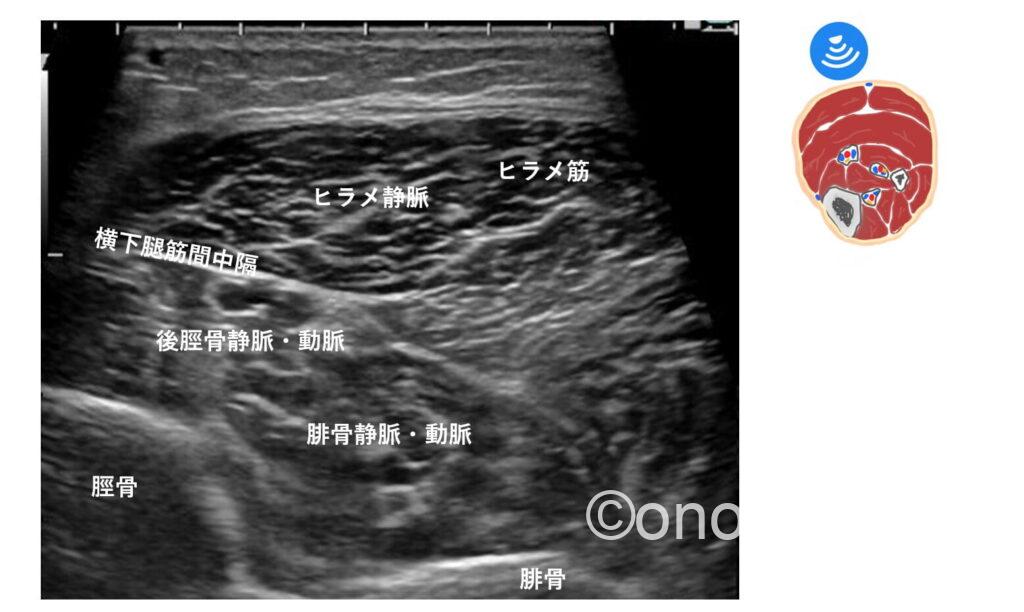

横下腿筋間中隔(TIMS)というヒント

TIMS:Transverse Intermuscular Septum は、浅層にあるヒラメ筋と、深層にある長母趾屈筋(FHL)や長趾屈筋(FDL)の間に介在する線維性の組織です。

文献によると、後脛骨動脈がTIMSへの直接的な血流供給源(栄養血管の供給元)となっているため隣接して走行しているとの事。

後脛骨動脈と静脈は並走しているので(動脈を挟んで静脈が2本走行している)TIMSに隣接している静脈・動脈→後脛骨静脈・動脈として認識出来るのではないかと思います。

個人的には、脛骨とヒラメ筋の間を滑るように走行している血管のイメージです。